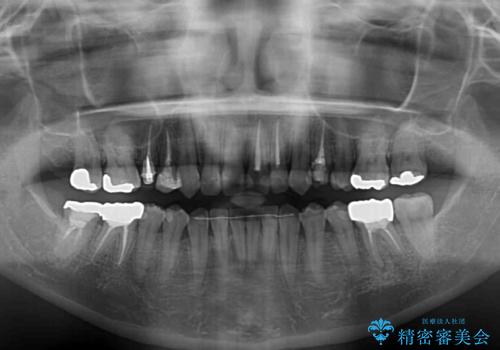

矯正治療後半に下顎左右奥歯をセラミッククラウンにて補綴し、その後インビザラインによる歯列の仕上げを行うこととしました。

下顎前歯の叢生が速やかに改善されたため、1年3か月で治療を終えることができました。

下顎前歯は後戻りを起こしやすいため、舌側を細いワイヤーで固定することで後戻り対策を行っています。